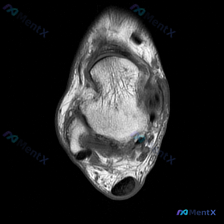

给大家分享一份足部MRI读片病例,整理了完整的分析思路,一起来讨论一下。 病例影像基本信息 这是一份足部前足区域(跖骨头/趾骨近端水平)的横断面MRI T2序列图像,核心观察结果如下: 1. 骨骼:中央跖骨头/趾骨骨皮质呈低信号,骨髓腔信号正常 2. 软组织:骨骼周围可见广泛不均匀信号异常,T2序列...